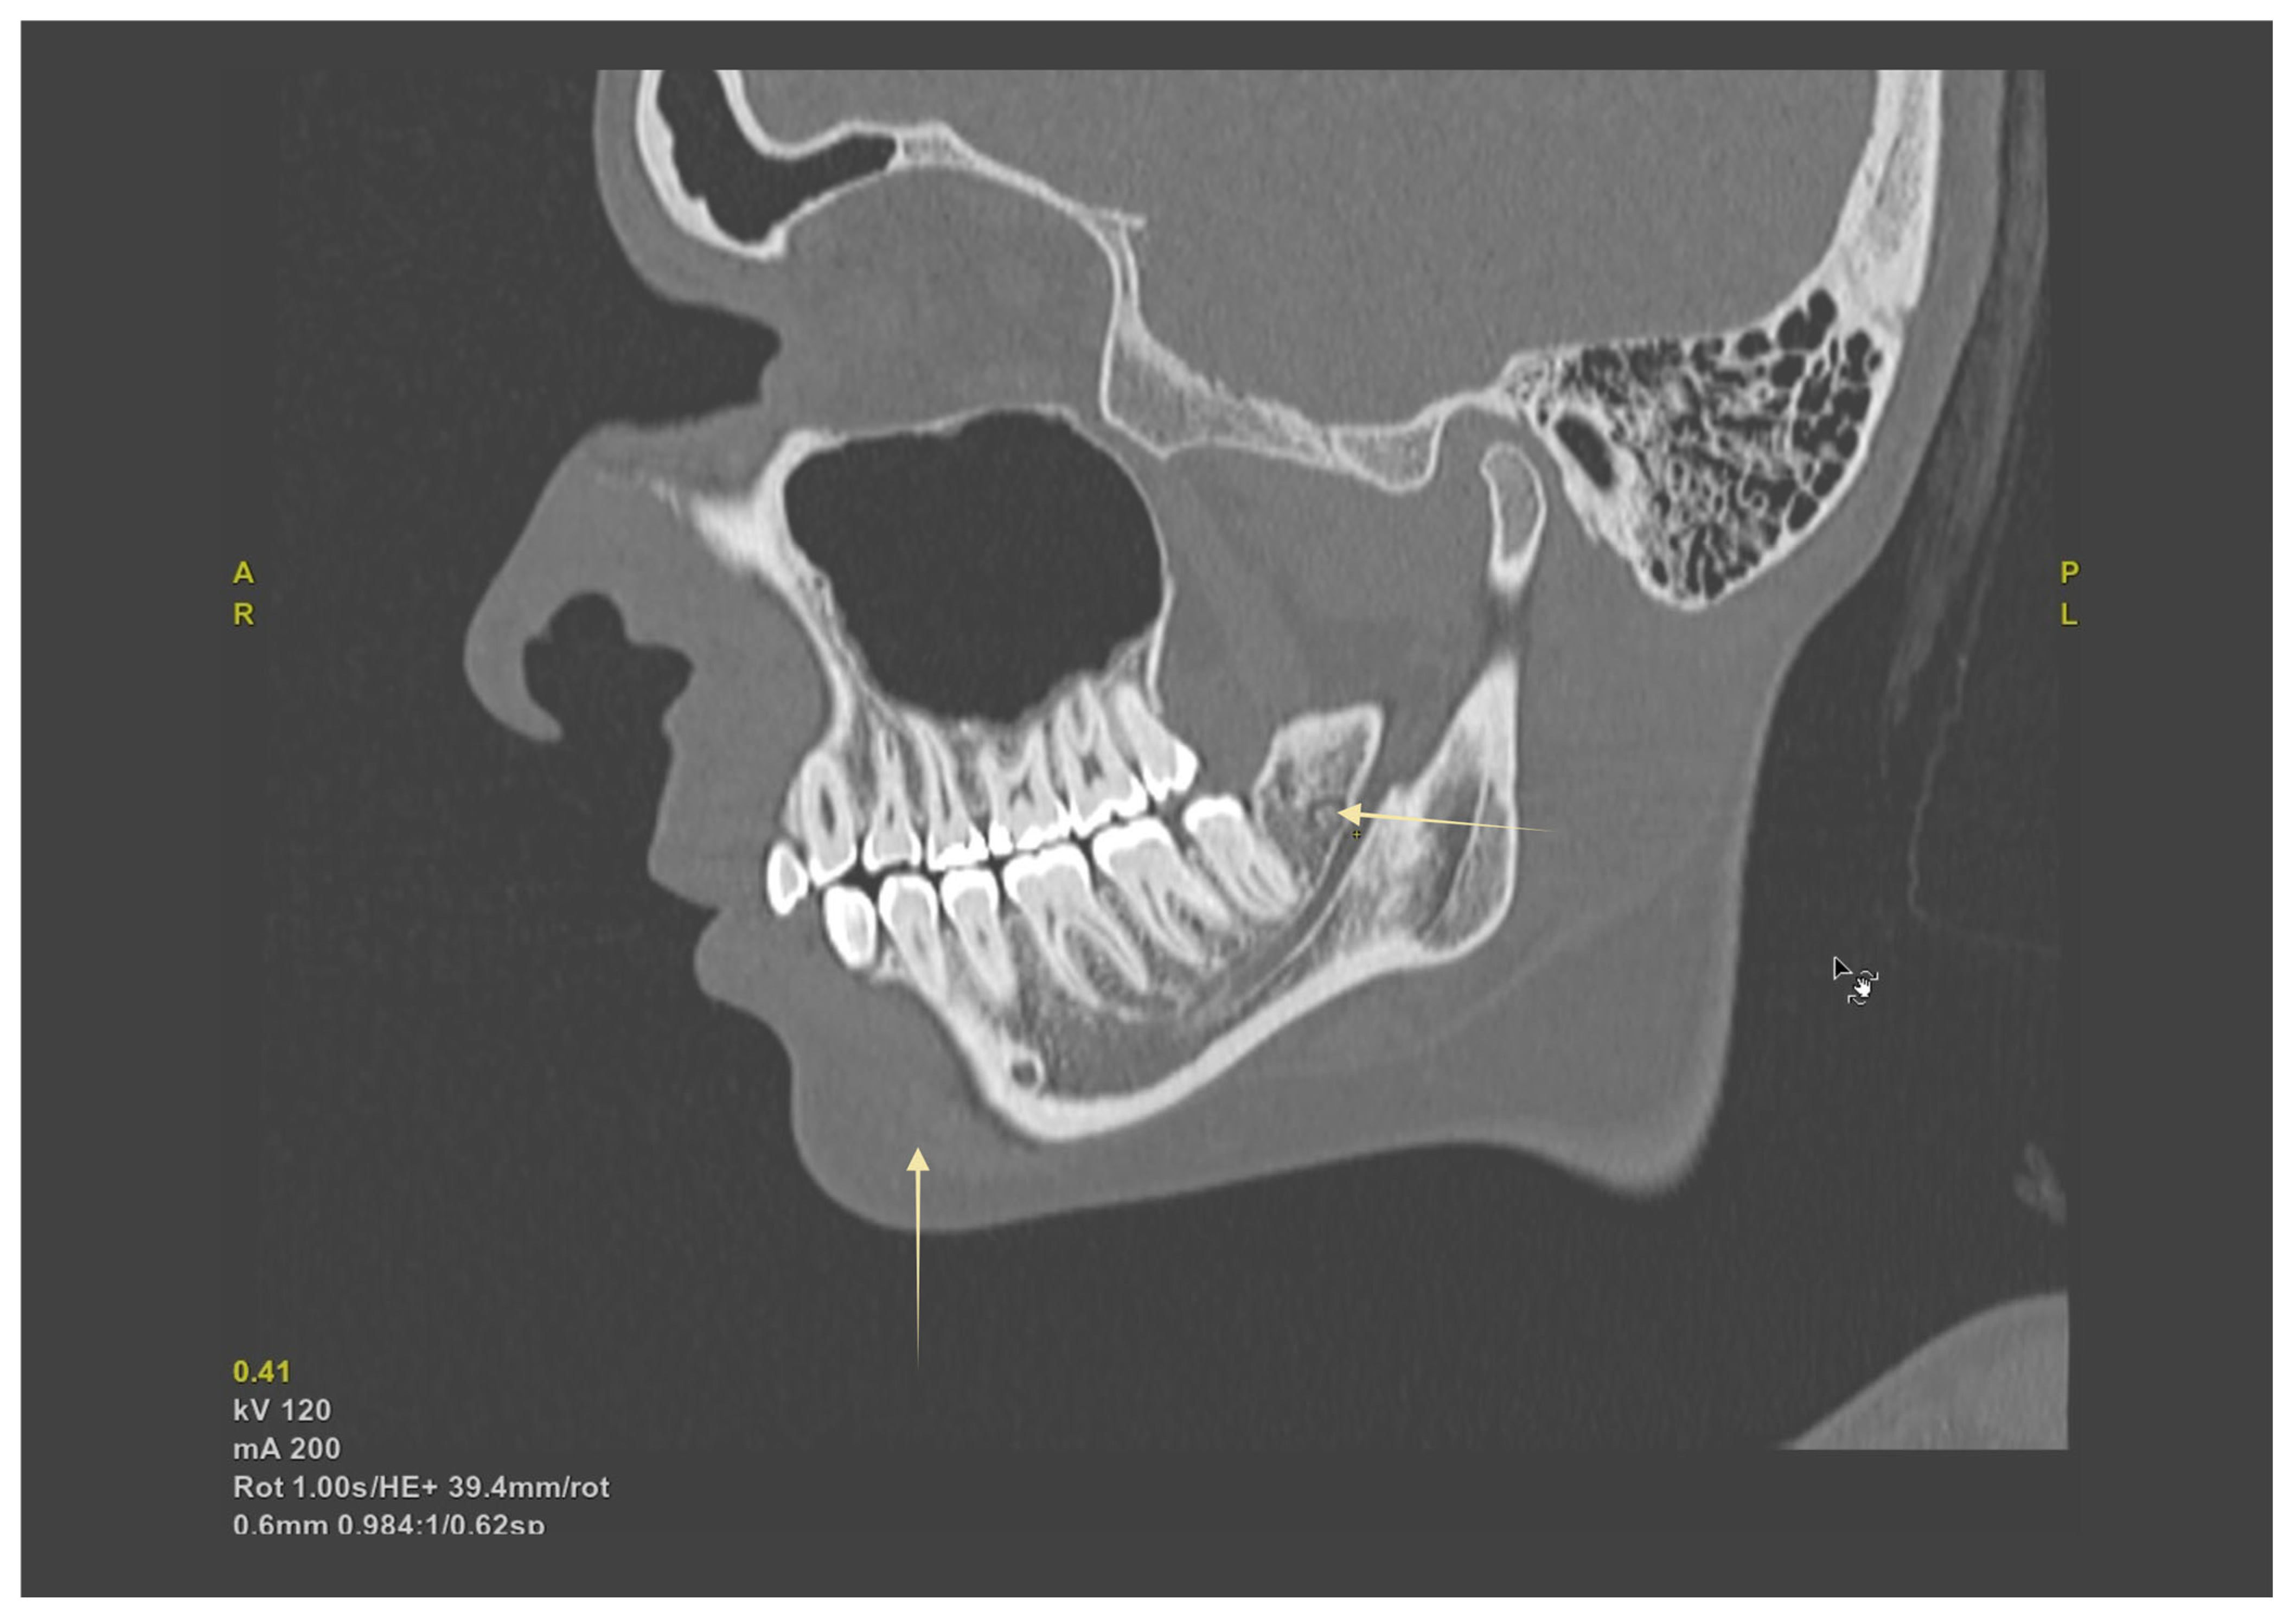

Figure 6. Oblique-sagittal CBCT reconstruction demonstrating the course of the mandibular canal (MC). The yellow arrows indicate the canal trajectory within the mandibular body and its proximity to the molar roots, serving as key landmarks for preoperative assessment and surgical planning.

Surgical extraction of mandibular third molars poses a significant risk for IAN injury, especially in the presence of RMCs or HMC. Undiagnosed RMC variants can cause unexpected intraoperative hemorrhage and postoperative neuropathy if transected during flap elevation or bone removal [12,16]. Similarly, an HMC located close to tooth apices limits surgical space, increasing the risk of nerve stretch or compression injuries [2,28]. Preoperative CBCT imaging significantly improves the detection of these variations [8,12,25], facilitating tailored surgical techniques, such as coronectomy to avoid nerve entrapment or modified flap designs to circumvent accessory nerve branches [3,39]. When proximity is high, prioritize conservative ostectomy, consider coronectomy, and plan flap/suture strategy to avoid accessory foramina and the retromolar foramen (see Table 5). Figure 6 shows a sagittal CBCT with an impacted third molar and the MC in close proximity, illustrating why CBCT mapping can alter the choice of approach (e.g., coronectomy, modified flap).